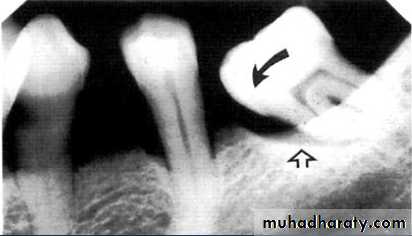

3.Furcation involvements:

Bone loss in the furcation area of the roots which is evidence of advanced disease in multirooted

teeth.

Initially seen as widening of the PL space at the crest of

the furcation . As lesion progresses, the bone

loss progresses apically.

Mild/moderate/sever.